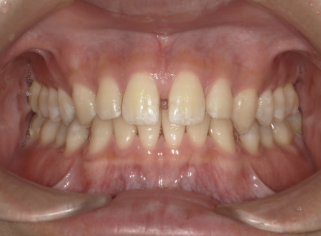

軽度すきっ歯症例画像

軽度(目安:前歯のすき間が1〜2mm程度/1〜2か所)

見た目が少し気になるレベルで、噛み合わせに大きな問題がない状態です。ワイヤー矯正やマウスピース矯正で前歯の位置・角度を整え、すき間をゆっくり閉じていく治療が中心になります。

中等度すきっ歯症例画像

中等度(目安:2〜4mm程度のすき間/複数の歯の間にすき間がある)

笑ったときや写真で、はっきりすき間が分かる状態です。矯正治療で前歯・奥歯の位置や噛み合わせをセットで整えることが多く、必要に応じて歯の形を少し整えたり、アタッチメントやゴムなども併用しながら治療していきます。

重度すきっ歯症例画像

重度(目安:4mm以上の大きなすき間/何本も歯の間にすき間がある・歯の本数不足や顎とのアンバランスを伴う)

すき間が大きく、歯の本数不足や顎の大きさの差など、いくつかの要素が重なっているケースです。矯正で歯並びと噛み合わせの土台を整えたうえで、被せ物・詰め物などの補綴治療を組み合わせて、歯の形や大きさも一緒に整えていく長期的なプランが必要になることがあります。